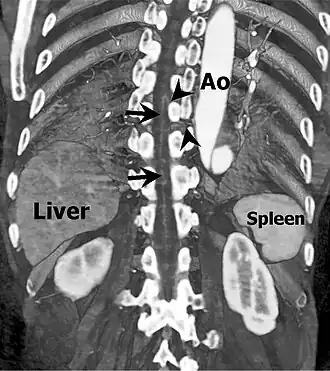

![]() Coronal slab volume rendering image of CT aortography shows artery of Adamkiewicz entering spinal canal(arrowheads) and joining the anterior spinal artery (arrows) after a hairpin turn. | |

The artery has a characteristic "hairpin" turn on the cord surface as it first courses superiorly, then turns inferiorly. In 75% of people, it originates on the left side of the aorta between the T8 and L1 vertebral segments.[11] In addition to being able to be either right or left-sided, the vessel can arise from a lumbar artery instead of from the aorta.[5]